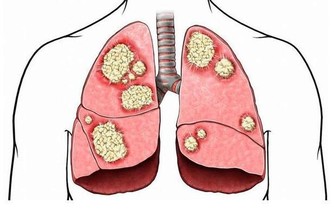

血管是我們身體的運輸渠道,如果血管裡出現了“髒東西”的話,這些“髒東西”會隨著血液的流動遍布人的全身,“髒東西”多了還會堵住血管,危害極大。

血管中的“臟東西”指的是甘油三酯、膽固醇,隨著人年齡的增大,這些“臟東西”會在血管壁上慢慢累積,導致血液流動受阻,這就是老年人更容易得腦血栓、心腦血管病、高血壓等疾病的原因。

血管堵塞很危險,特別是中老年人群。小堵容易誘發中風,高血壓等疾病,而嚴重的堵塞會直接導致腦血栓、腦梗塞或直接猝死。所以在平時,清理血管很重要!